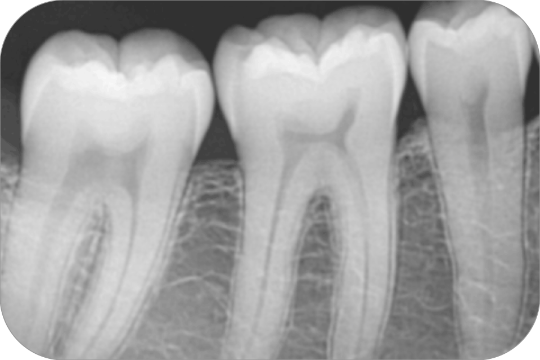

Aleta de mordida